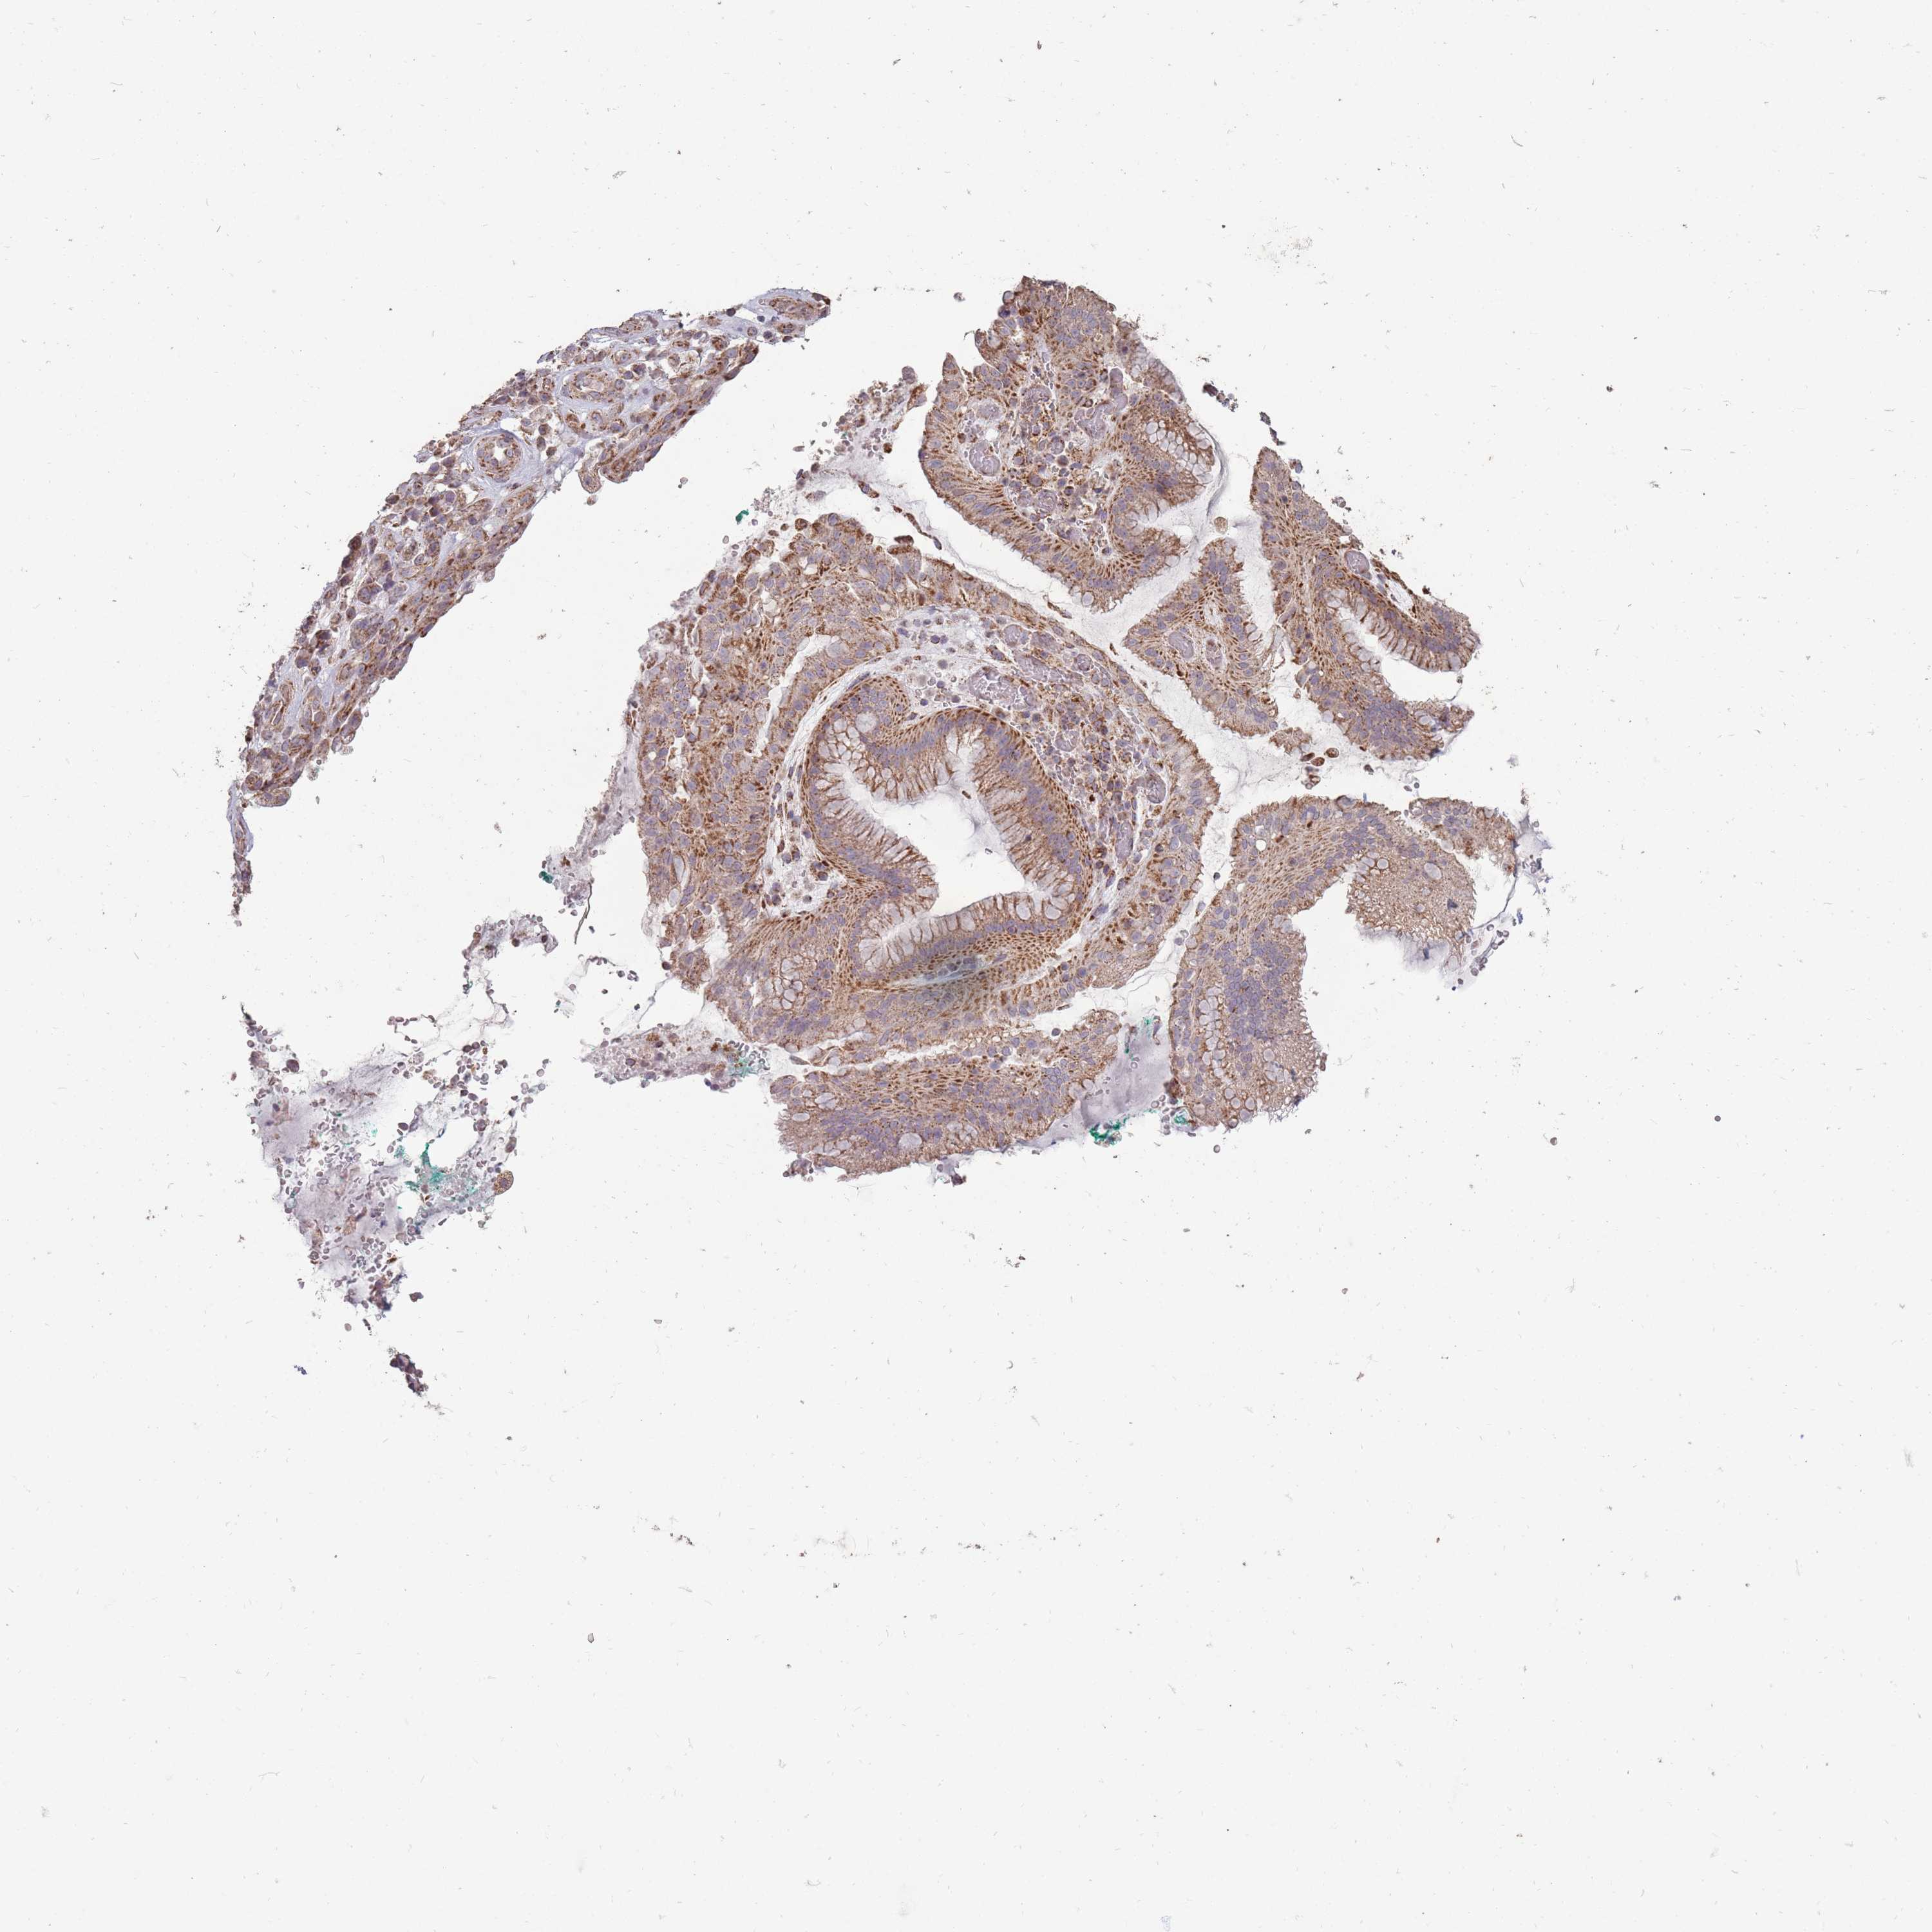

STOMACH CANCER - Protein expressioni

A mouse-over function shows sample information and annotation data. Click on an image to view it in a full screen mode. Samples can be filtered based on level of antibody staining by selecting one or several of the following categories: high, medium, low and not detected. The assay and annotation is described here.

Note that samples used for immunohistochemistry by the Human Protein Atlas do not correspond to samples in the TCGA dataset.

Antibody stainingi

Antibody staining in the annotated cell types in the current human tissue is reported as not detected, low, medium, or high, based on conventional immunohistochemistry profiling in selected tissues. This score is based on the combination of the staining intensity and fraction of stained cells.

Each image is clickable and will lead to virtual microscopy that enables deeper exploration of all samples and also displays staining intensity scores, fraction scores and subcellular localization as well as patient and tissue information for each sample.

Antibody HPA051398

Staining

High

Medium

Low

Not detected

Intensity

Strong

Moderate

Weak

Negative

Quantity

>75%

75%-25%

<25%

None

Location

Nuclear

Cytoplasmic/membranous

Cytoplasmic/membranous,nuclear

Adenocarcinoma, NOS